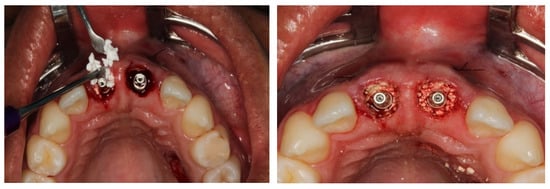

2.5. Surgical Procedures

3. Results

Result and Follow-Up